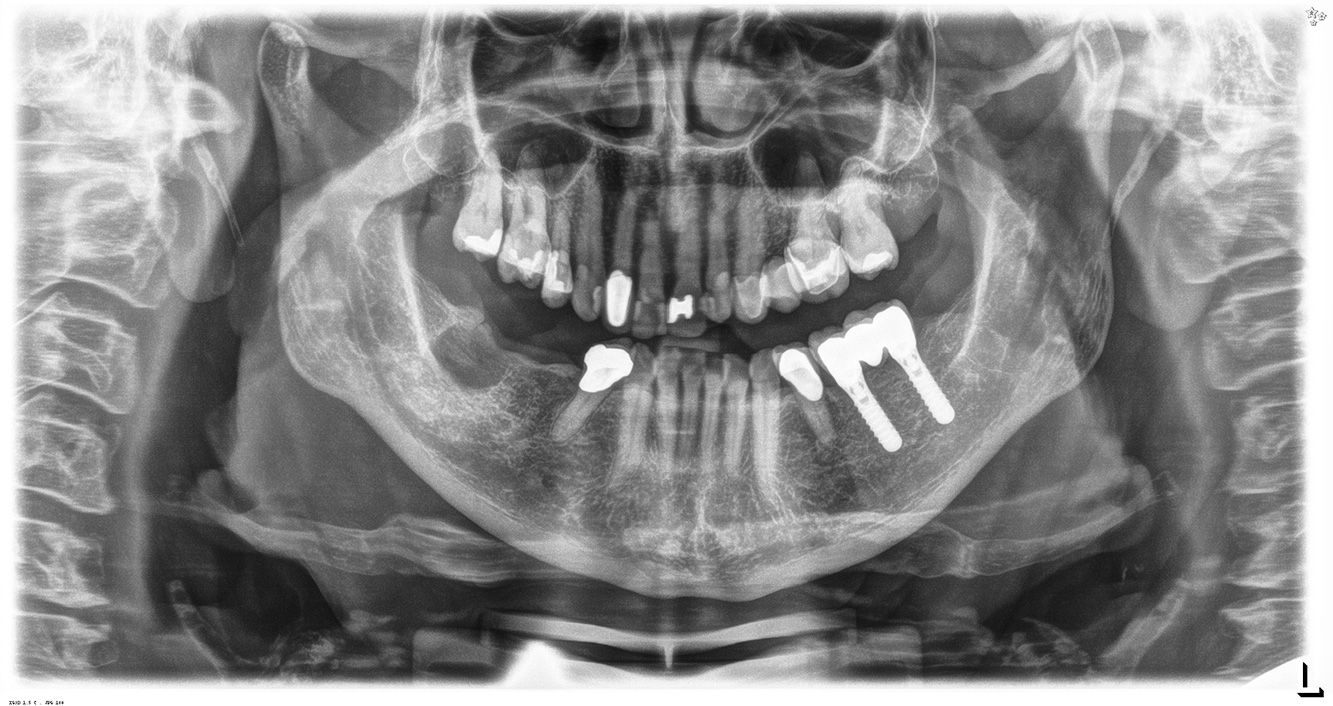

The 68-year-old patient has no general health conditions and is not taking any medication that may be relevant to her oral health, and her lifestyle does not pose any particular risk. The patient has two dental implants (3rd quadrant, for five years) and a previous case of periodontal disease (stage IV, grade B periodontitis) with tooth loss. Currently the periodontal conditions are stable. However, periodontitis significantly increases the biological complications of implantations and there is a risk of implant loss (21). Four recommendations can be determined for the prophylaxis session.